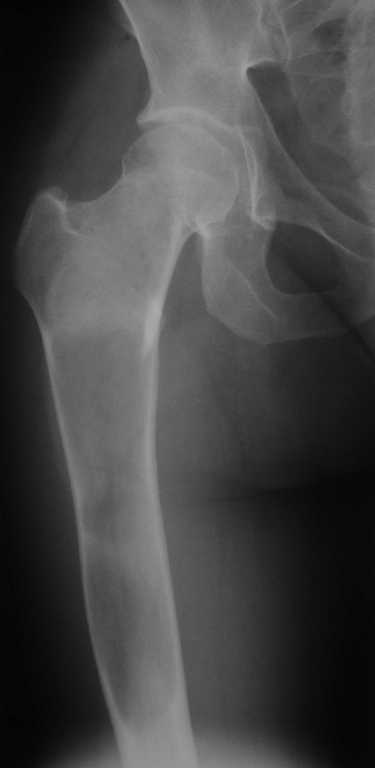

Уважаемые коллеги! В клинику поступила молодая женщина 35 лет с

жалобами на интенсивные боли в области правого бедра, носят спонтанный

характер, имеются "ночные" боли. Движения в правом тазобедренном

суставе в полном объёме, практически безболезненные. По результатам

x-ray диагностики выявлен патологический очаг, занимающий весь

проксимальный отдел и 2/3 диафиза правой бедренной кости. Другие

трубчатые кости верхних и нижних конечностей - без очагов поражения.

Имеется небольшой (1,5х2,5 см) очаг в крыле правой подвздошной кости.

По результатам трепанобиопсии проксимального отдела правой бедренной

кости - фиброзная строма и костные балки, без атипии.